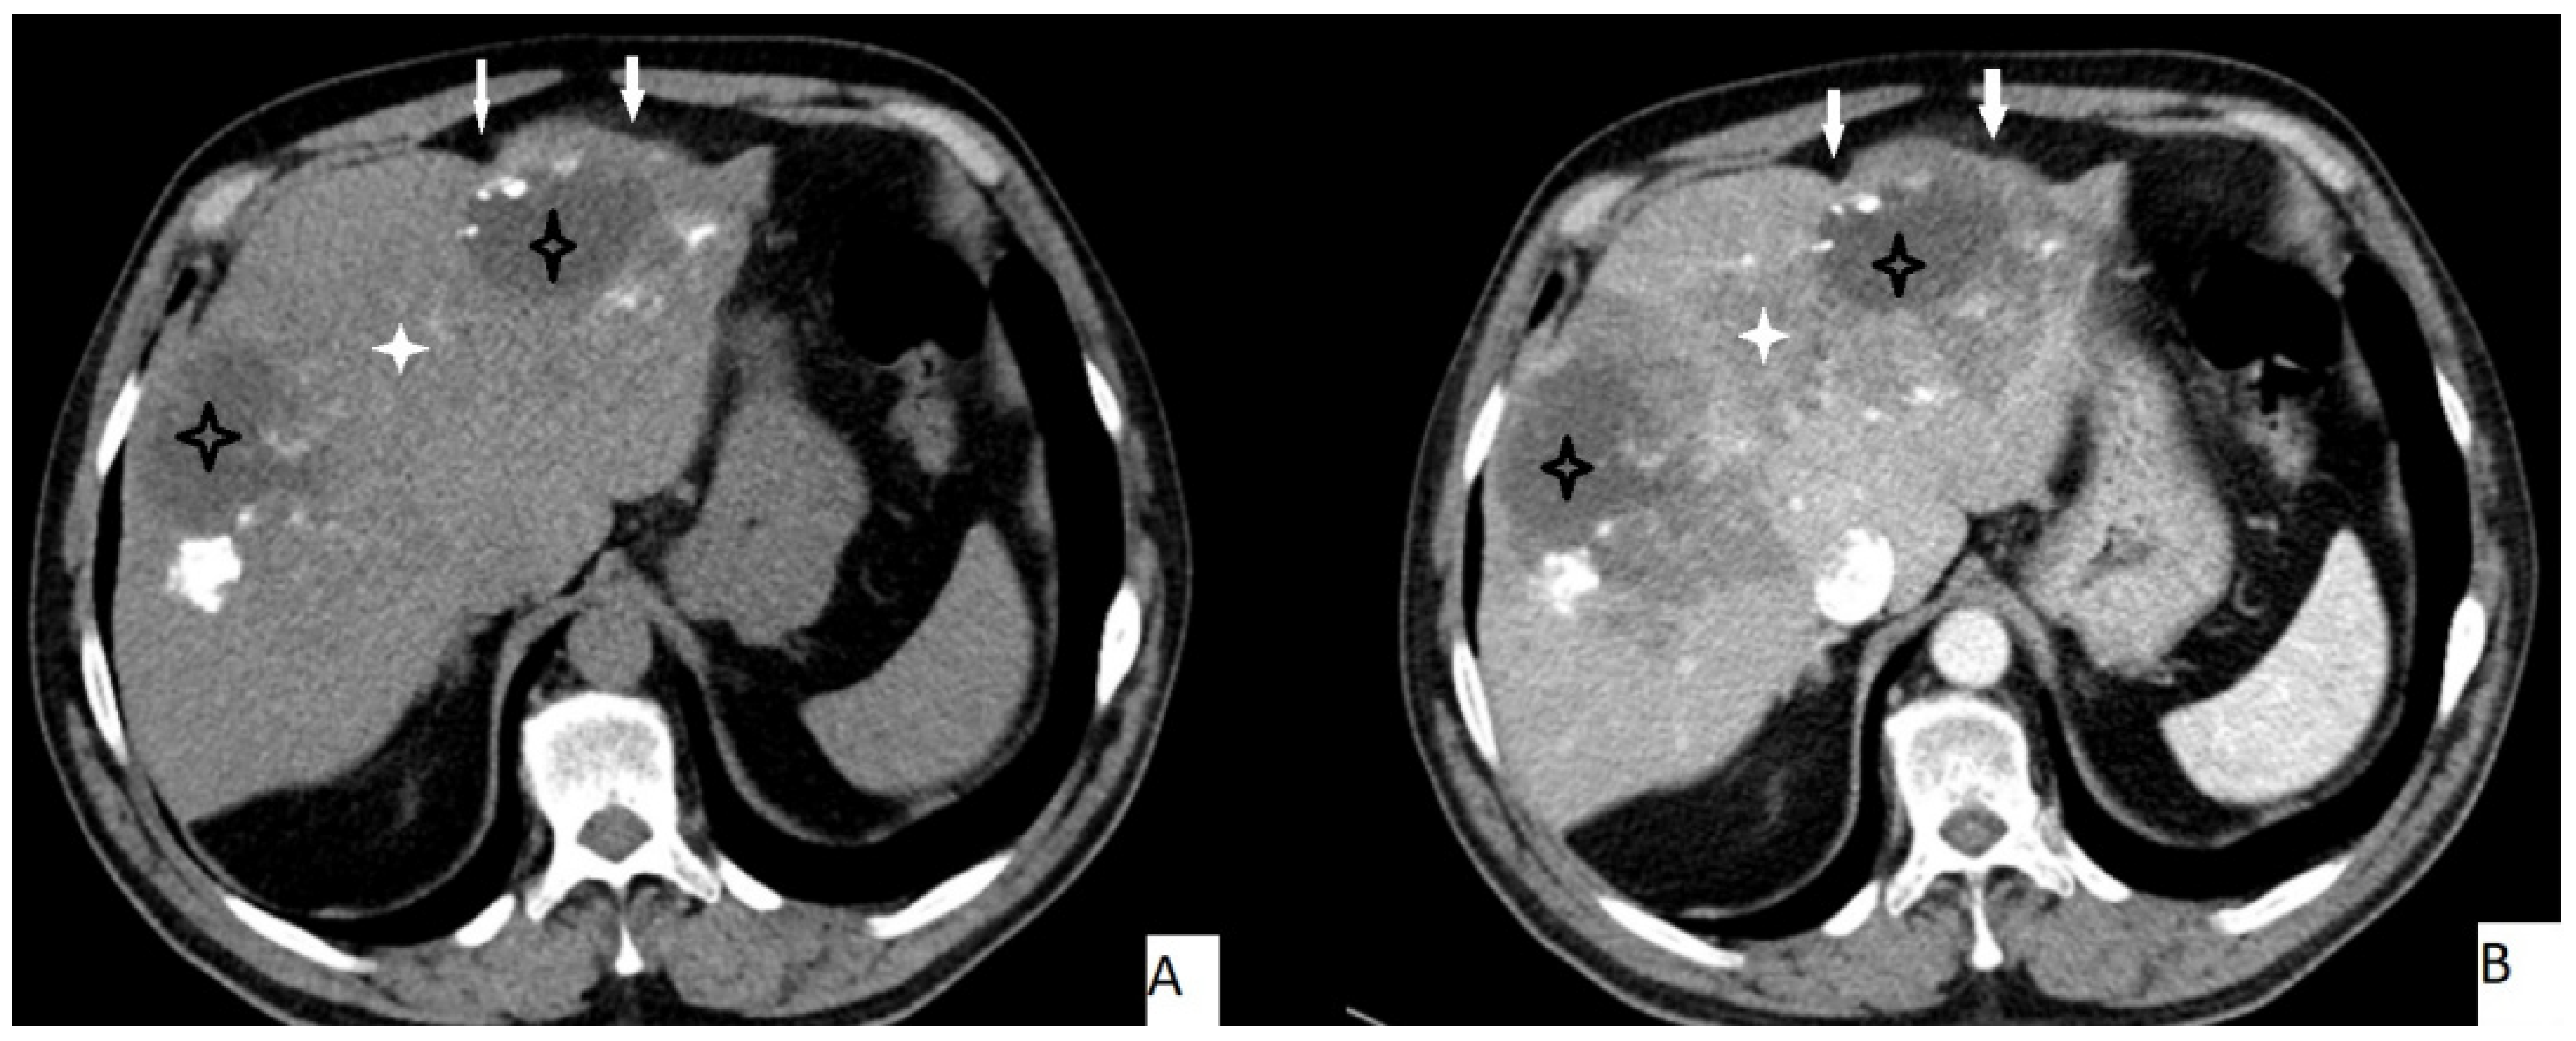

The most frequently encountered CT pattern was a heterogeneous mass with calcifications and hypoattenuating areas (72.3%). Most of the lesions had irregular contours (85.4%), 85.4% lacked contrast enhancement, 77.4% of the lesions had calcifications, and atrophy and capsular retraction was present in 10.7% of the lesions (Figure 2 and Figure 3). Table 3 details the distribution of CT appearances.

Figure 2.

51-year-old male. Hepatic lesion with irregular contours and calcifications on precontrast axial CT (A). On portal venous images (B), no enhancement is present in the lesion. Central necrosis can be seen (A,B—black star). Perilesional enhancement (B—white star) and capsular (A,B—arrows) retraction are present.